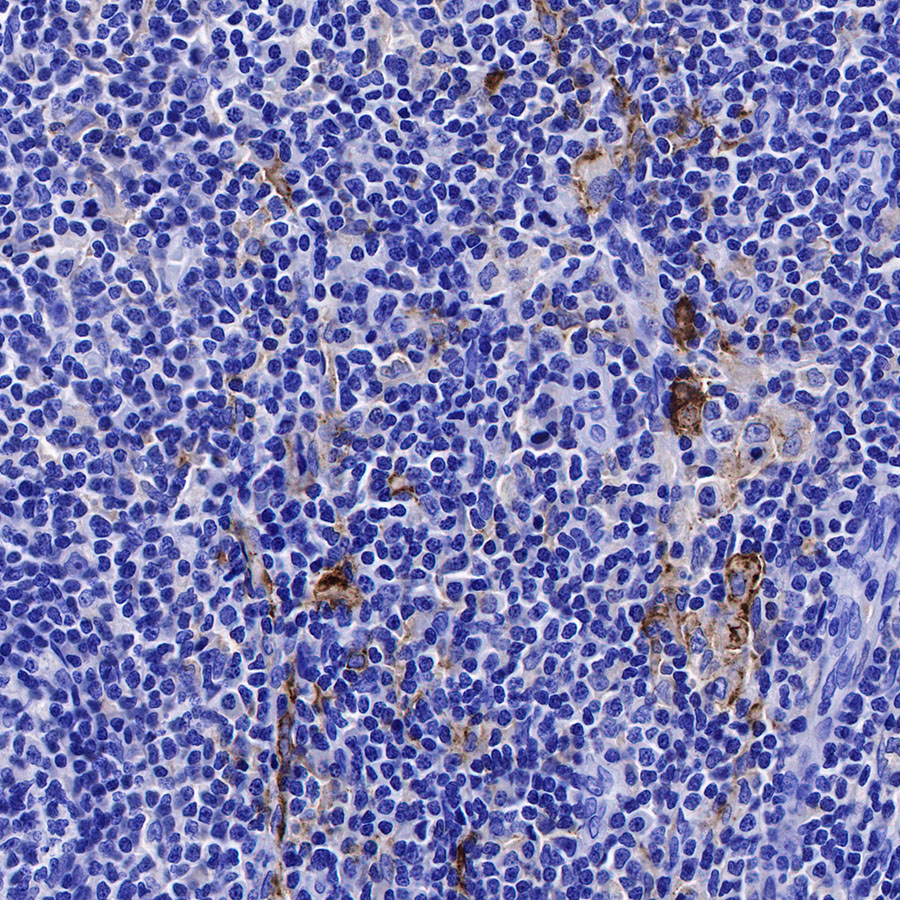

Immunohistochemistry

IHC shows positive staining in paraffin-embedded human placenta. Anti-CD169 antibody was used at 1/250 dilution, followed by a HRP Polymer for Mouse & Rabbit IgG (ready to use). Counterstained with hematoxylin. Heat mediated antigen retrieval with Tris/EDTA buffer pH9.0 was performed before commencing with IHC staining protocol.